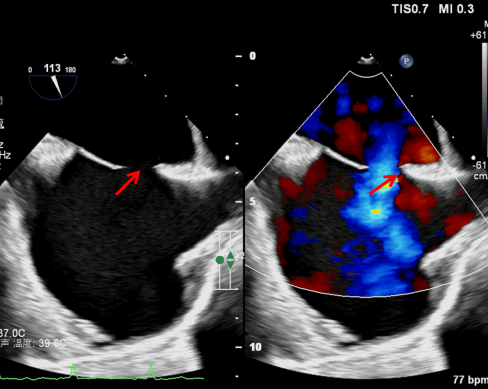

一年前,陳女士在勞累、受涼后就會(huì)感到胸悶、氣促,反復(fù)伴有頭痛,她誤以為是感冒,所以長期口服頭痛粉治療。一個(gè)多月前,陳女士再次出現(xiàn)頑固性頭痛伴心慌胸悶,遂來我院心血管內(nèi)科求治,于長青主任接診后通過認(rèn)真詢問病情和系統(tǒng)查體,判斷為先心病,為患者進(jìn)一步行心臟超聲證實(shí)為房間隔缺損,缺損直徑達(dá)到了驚人的18.4mm!

為確保手術(shù)成功,術(shù)前介入團(tuán)隊(duì)會(huì)同超聲醫(yī)學(xué)科副主任(主持工作)盧岷多次進(jìn)行手術(shù)模擬路演,制定詳盡的手術(shù)方案及各種應(yīng)急預(yù)案。術(shù)中,于長青主任帶領(lǐng)謝鳳副主任醫(yī)師、劉大偉副主任醫(yī)師按照手術(shù)方案有條不紊地實(shí)施局麻、血管穿刺,在超聲及DSA引導(dǎo)下,通過鞘管精準(zhǔn)將封堵傘送至房間隔缺損部位成功釋放,多角度投影及超聲證實(shí)完全封堵缺損的房間隔,手術(shù)成功。術(shù)后第二天,陳女士便能自行下床活動(dòng),目前已康復(fù)出院。